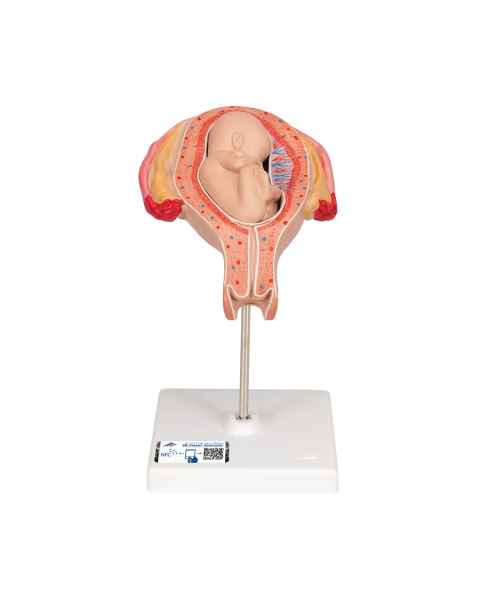

Female anatomical models are an ideal teaching aid to help educate both students and patients. Our extensive selection of female anatomy models includes female pelvic models, pregnancy series models, pelvis skeleton models, delivery/childbirth simulators, clinical breast trainers and self-exam models, uterus/ovary models, and more. Teaching simulators and self-exam models are excellent for educating students and patient education.

For example, the Wearable Breast Self-Exam Model can be easily worn, in order to better train and practice breast self-examination. Our line of prevention and detection models includes the Realistic Left Breast Model, Uterus/Ovary Model with Pathologies, Model of the Female Breast, and the Clinical Breast Trainer. Obstetricians will benefit from owning female anatomy figures of uteri and pelvises with fetuses inside, as well as sets of models that demonstrate the stages of fertilization. Women, particularly first-time mothers, will appreciate having a female education model that clearly illustrates the pregnancy process and what exactly is occurring inside of their body.